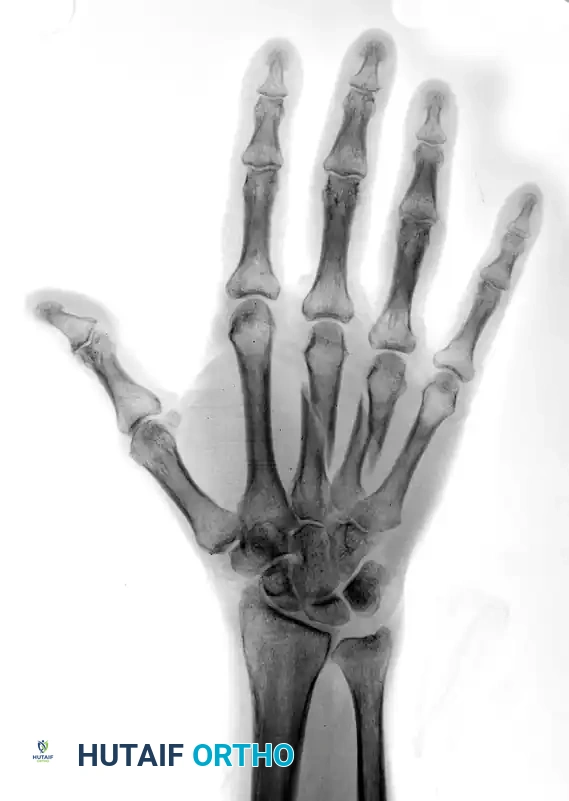

Preoperative Imaging:

FIGURE 67-42 A: Preoperative AP radiograph showing shortened and oblique middle and ring metacarpal fractures.

FIGURE 67-42 B: Preoperative oblique radiograph demonstrating the fracture geometry, which is highly suitable for interfragmentary fixation.

Postoperative Imaging:

The fractures were reduced anatomically. Lag screws were placed to provide interfragmentary compression. To neutralize the sagittal bending moment—particularly in the ring metacarpal—a supplemental 24-gauge cerclage wire was applied.

FIGURE 67-42 C: Postoperative AP radiograph showing anatomic reduction and rigid fixation.

FIGURE 67-42 D: Postoperative oblique radiograph. Note that the sagittal bending moment of the ring metacarpal shaft fracture was successfully offset by the supplemental 24-gauge cerclage wire fixation.